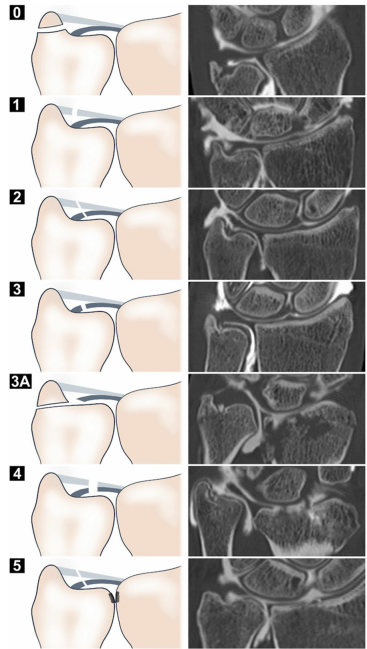

TFCC 손상 분류법

TFCC는 구조가 복잡해서

어디가 문제인지 체계적인 진단이 되야

수술할지가 결정됩니다.

@ DOI:10.1016/j.arthro.2012.04.152

기본적으로

**팔머 분류(Palmer Classification)로

2타입 9종류로 나누는데요.

다쳐서 외상성이면 '타입 1' 이고요.**

A : 관절연골 중심부 파열

B : 척골쪽 부착부가 떨어져 나감

(골절 동반 O/X)

C : 원위부 손상

D : 요골쪽 부착부가 떨어져 나감

4가지 서브타입으로 나눠집니다.

많이 쓰거나 척골이 길어서 충돌되면서

점점 닳아서 생긴건

퇴행성 병변으로 **'타입2'입니다.

A : 관절연골 닳아 얇아짐

B : 관절연골 마모 + 주변 연골 손상

C : 관절연골 파열 + 연골 손상

D : C에 월상삼각인대 파열까지

E : D에 손목 관절염까지 진행

5가지 서브타입으로 나눕니다.

9가지 중에 가장 흔한 타입은

외상성 중 B형인데요.

@ https://doi.org/10.1186/s12891-020-03321-2

안정성에 중요한 깊은 층과

상대적으로 덜 중요한 얕은 층을

구별하지 않는다는 한계점이 있습니다.

요즘엔 보통 Atzei 아체이 분류법을

함께 사용해서 수술 여부를 결정합니다.